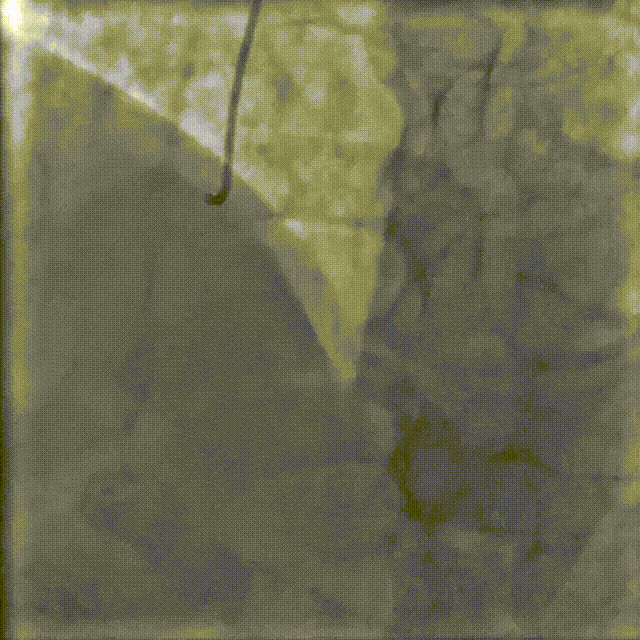

图5.RCA术前FFR

测量FFR结果为0.74(图5),verify为1mmHg。